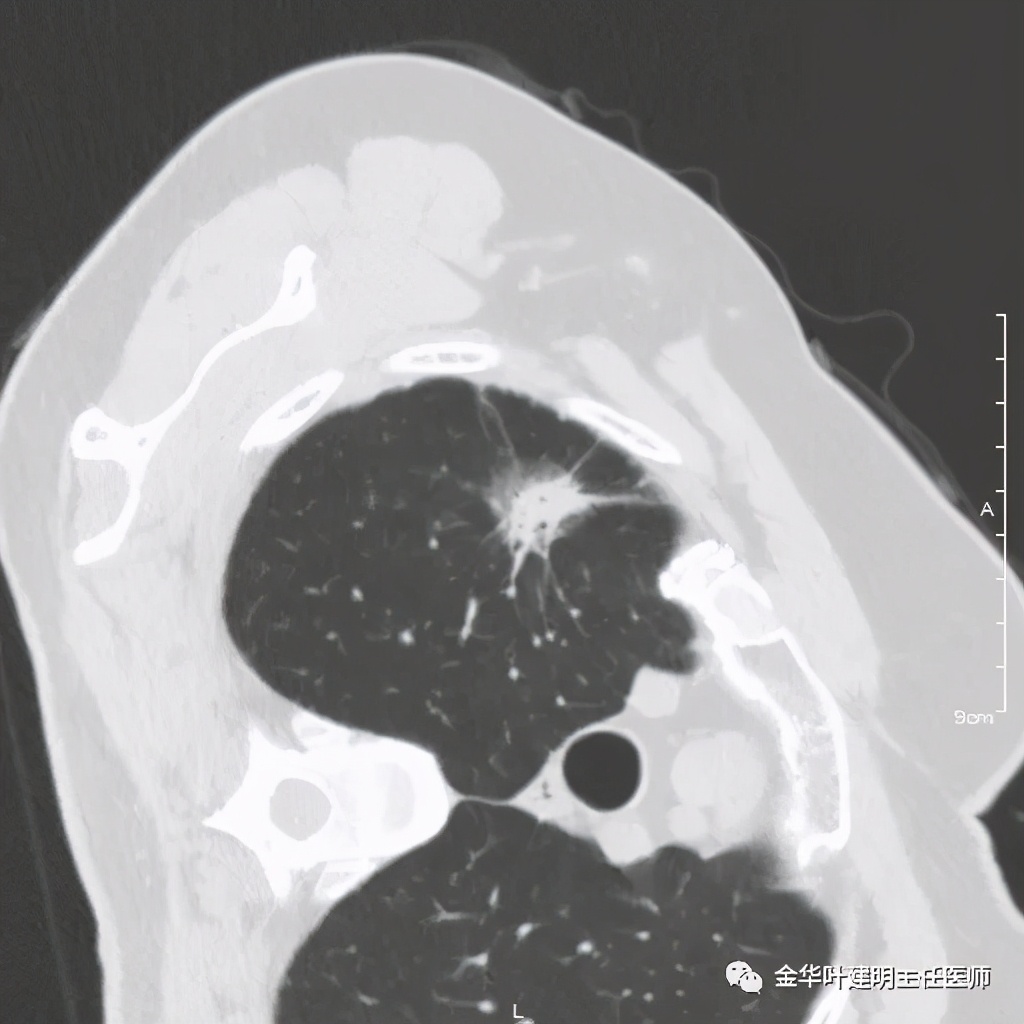

七、浸润性腺癌的其他型:

上图病例为实性,病理上实体型占80%,腺泡型占20%

上图此例也是实性结节,病理报告:实体型伴神经内分泌;

上图此例的实性肿块,病理是:微乳头为主,部分实体型,当时没注明占比;

上图此例实性结节,是实体型,我们发现其影像特征: 病灶有浅分叶、细毛刺、支气管截断征、膨胀性,密度高而密 (比腺泡型实、比粘液癌高、比鳞癌或小细胞癌更具膨胀性)。

但是上面这几例,因为不管怎样的组合,都是实性密度+实性密度,这时仅从影像上就非常难以判断具体的亚型,不过,我们要根据相关的影像特征判断它为恶性,而且该尽早取得病理依据,能手术的要抓紧、不能手术的也要穿刺等得到病理类型的确诊后积极治疗,这就够了!